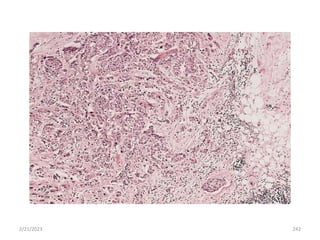

2/21/2023 241

2/21/2023 242